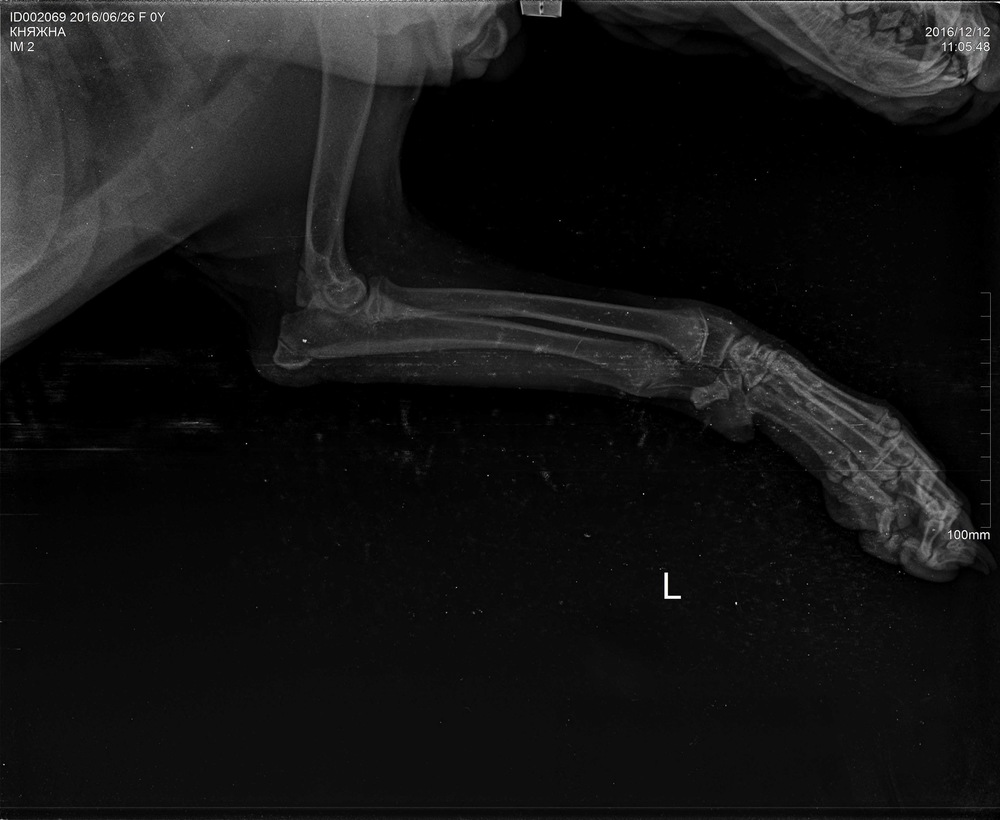

Рентгеновские снимки перелома лапы у кота: диагностика и лечение